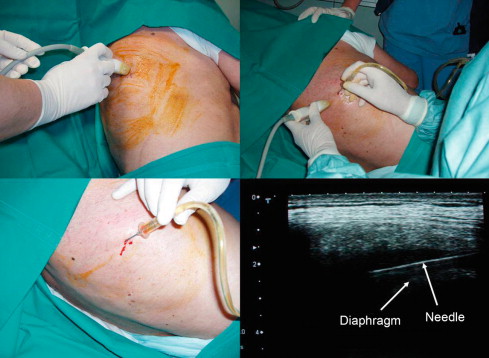

radiology department

Diagnostic Radiology

Interventional radiology (IR)